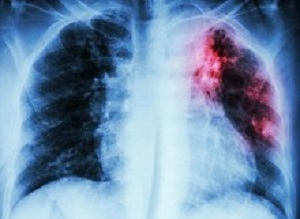

TuberculosisWhen one considers the TB numbers, it boggles the mind that it is not dominating the headlines, not a top priority for political parties or trade unions, and not one of the key issues in every single State of the Nation address, writes Marcus Low, a former head of policy at the Treatment Action Campaign (TAC) in Spotlight.

Low writes: “Almost half-a-million, more than 400,000 people, develop active TB every year in South Africa. By World Health Organisation estimates, over 100,000 people in South Africa die of TB every year. While, say, Ebola and listeriosis are also very serious, the numbers involved in those outbreaks are dwarfed by the scale of the TB epidemic. We have a deadly disease tearing through our communities, killing at an alarming rate – and yet, politically it is hardly raising a flutter.